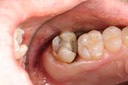

Joe Cha #29 pre-op